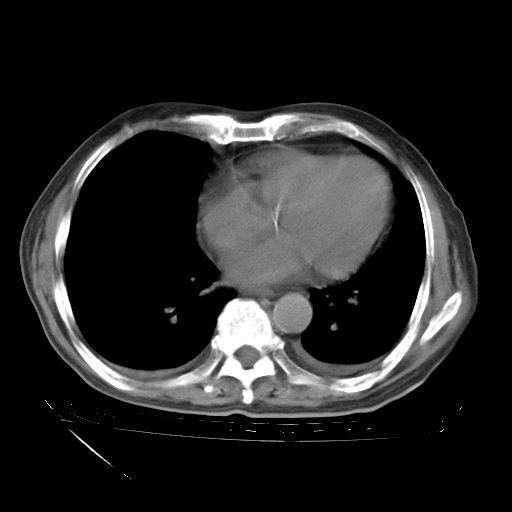

经过24天治疗,岳父的病情基本稳定。生活基本可以自理,可以下床活动。呼吸困难早已消失。体温基本正常。

只是甲强龙用80mg时血小板升到正常,改为60mg后又降到63×10*9/L。

主要治疗甲强龙80mg×14天,60mg×10天;同时抗结核(异烟肼+利福平+乙胺丁醇)。环磷酰胺0.1 tid 10天。

特别感谢胡教授、高管、桃子版主给出关键的治疗建议。桃版把所有肺部影像和全部临床资料请所在医院呼吸科、感染病科、结核科、临床免疫科专家会诊。临床免疫科专家制定了完整的治疗方案。